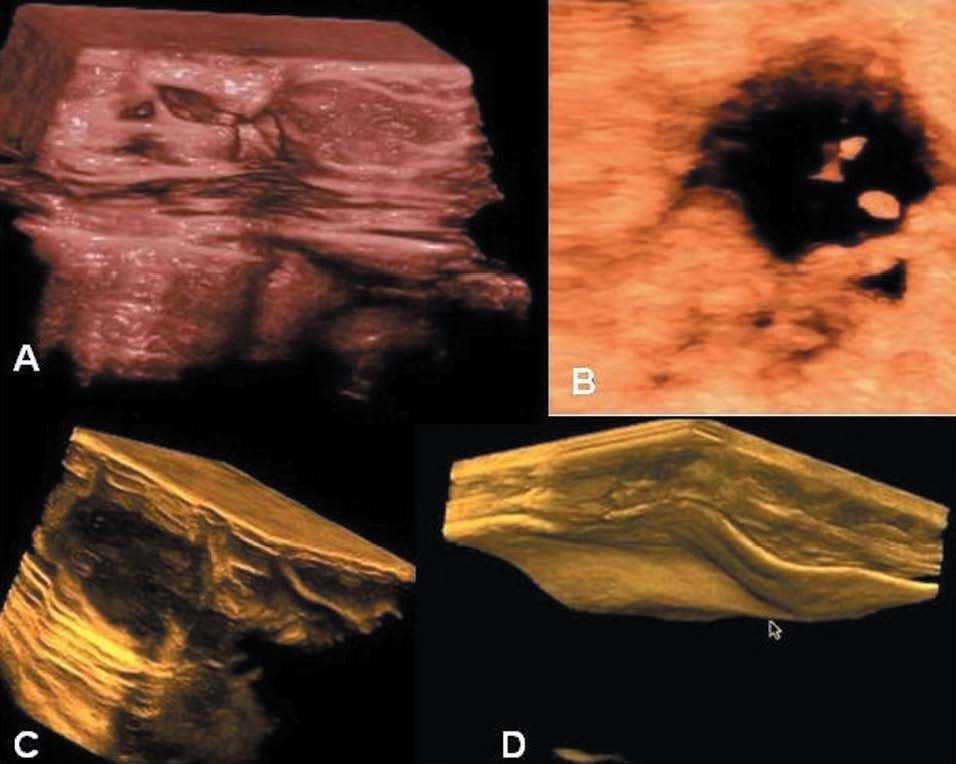

Patología mamaria

Tradicionalmente, el ultrasonido se ha utilizado como complemento de la mamografía para la detección de las alteraciones mamarias. Con el desarrollo de estas nuevas tecnologías se vislumbra un papel importante en el diagnóstico de las tumoraciones, sobre todo en el diagnóstico precoz, al incrementar notablemente la nitidez de la imagen obtenida (visión posible de microcalcificaciones) y aumentar la capacidad de análisis de la RDI por medio de las diversas modalidades de visualización, como las mostradas en la figura 11.

Figura 11.4D de mama. Otra excelente aplicación de esta nueva tecnología. A) Mastopatía fibroquística. B) Quiste con papilas y calcificaciones. C) Fibroadenoma. D) Prótesis mamaria mal colocada que hace ondas en su pared anterior. (Cedido gentilmente por L. Machado.)

Aunque hasta el momento los estudios realizados no muestran una diferencia significativa entre ultrasonografía 2D y 3D17,18, hay trabajos18 que señalan que la visualización del fenómeno de retracción en el plano de corte coronal en 3D tendría un significativo valor pronóstico para el cáncer de mama.